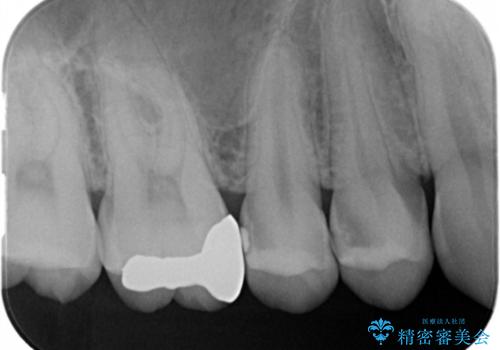

- 定期検診でレントゲンを撮影したところ虫歯があったので拡大鏡下で虫歯を取り除き、白い詰め物にて治療しました。

無事歯の神経を取らずに白い詰め物で治療する事ができました。

歯がズキズキ痛くなるという現象は歯の神経にまで虫歯が進行し歯髄炎になっている可能性が高く、神経を取らなければならなくなってしまいます。